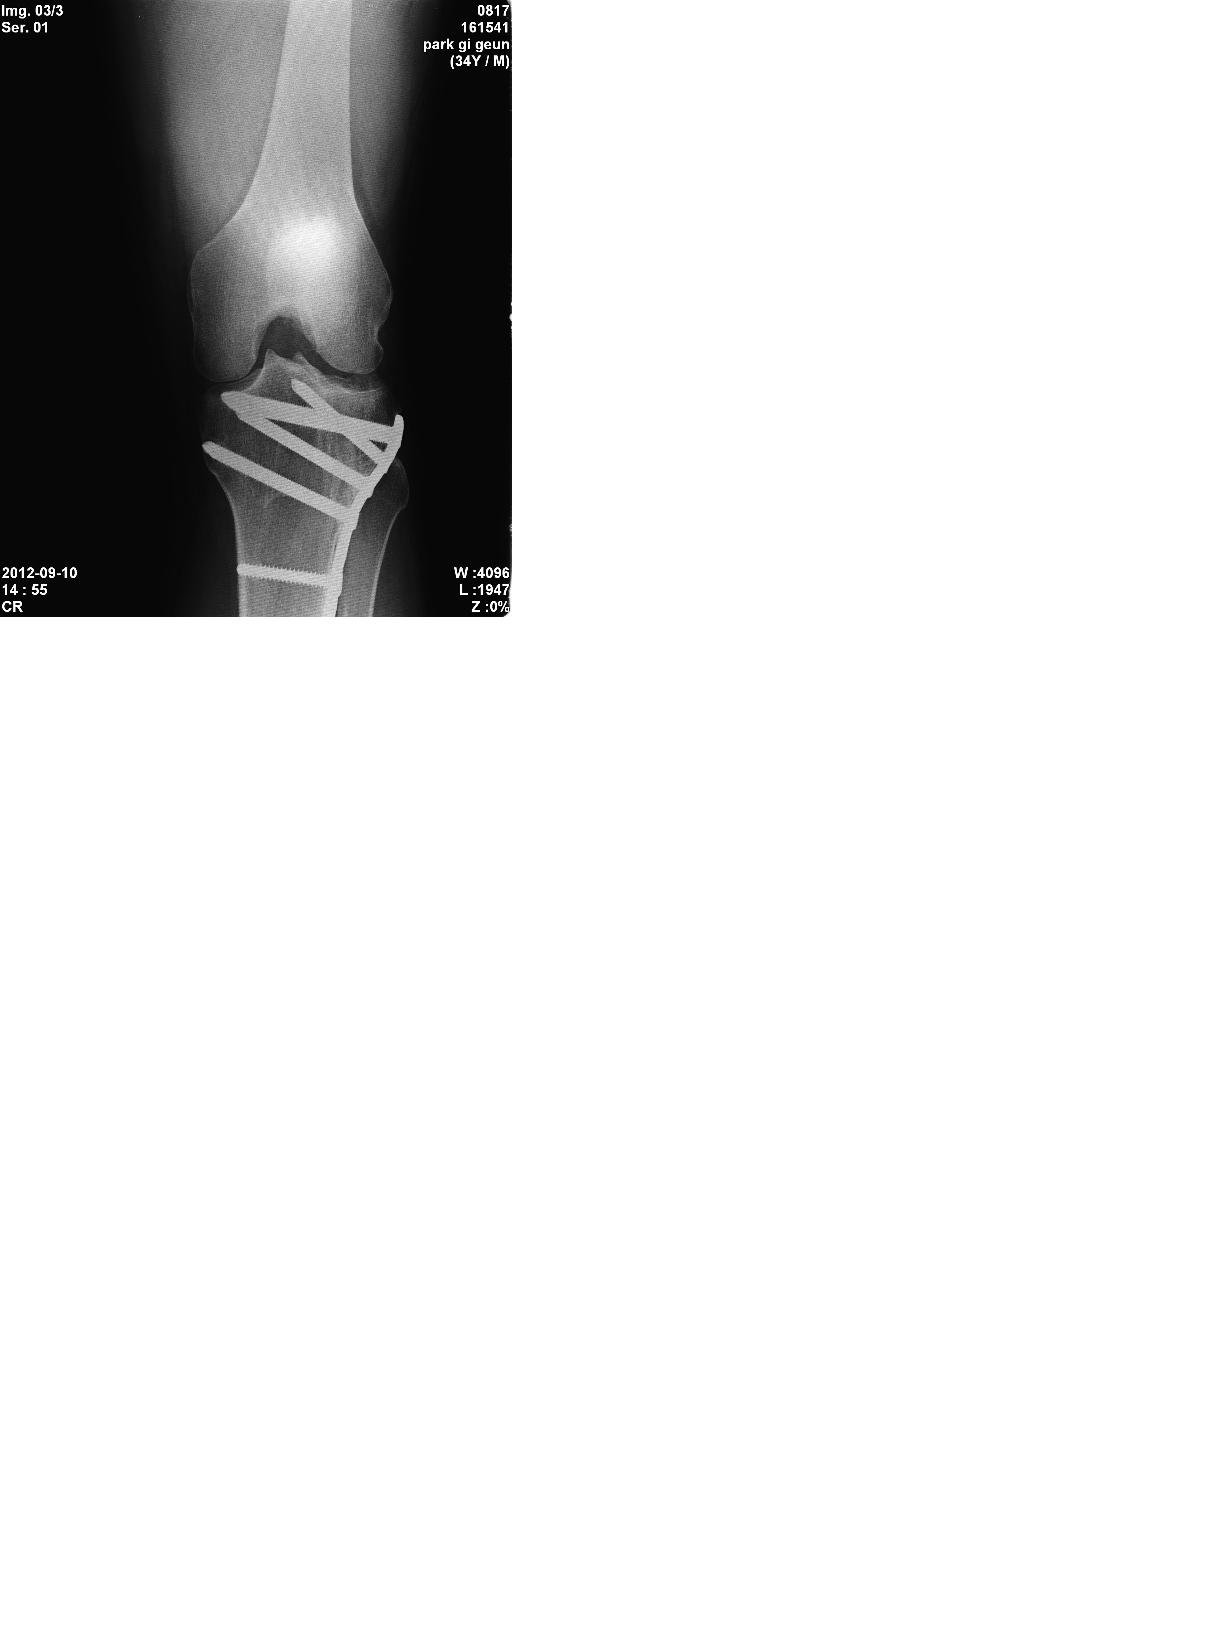

2005년 사고로 연골 떠받드는 부위에 금이가서 핀 고정술을 하였습니다

약간의 관절 강직으로 보행은 무리가 없으나 달리기와 점프 그리고 다 접히지 않는 관절 강직이 좀 있어요

장애 나올까요? ㅎㅎ  수술한 대학병원 교수님은 자존심때문인지 운동 좀더 합시다 이러는데 ㅡㅡ 5개월 넘개 재활 했는데 다 안구부려집니다 ㅠㅠ

전문가들의 답변을 기다립니다 ㅎ'제목 없음3.JPG 제목 없음1.JPG 제목 없음2.JPG

X-ray